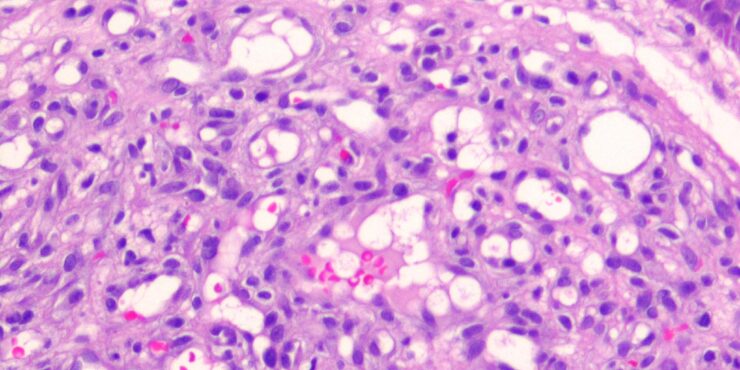

Read MorePyogenic granuloma = الورم الحبيبي التقيحي OLYMPUS DIGITAL CAMERA OLYMPUS DIGITAL CAMERA OLYMPUS DIGITAL CAMERA OLYMPUS DIGITAL CAMERA